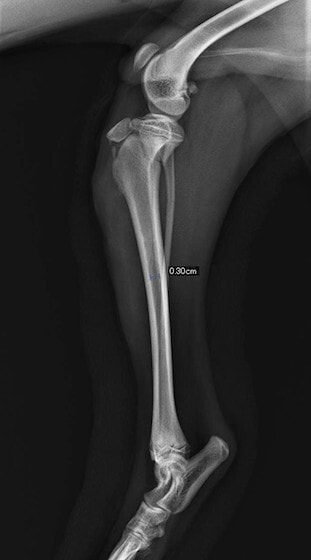

症例3:キルシュナーワイヤーのピンニングによる整復

ペルシャ猫 11ヶ月齢 雄

他院にて左大腿骨遠位の成長板骨折(salter-harrisⅠ型)が認められており、治療相談を目的として来院。当院にて、キルシュナーワイヤーを用いたピンニングにより骨折部位の整復を行いました。術後の経過は良好で、現在も経過観察中です。

術前レントゲン

術後レントゲン

機器

Arthrex社のターゲティングデバイスを用いてピンニングの位置を調整することで、確実な固定を行っています。当院ではこの手術器具以外にも、人の手術にも使用される様々な器具を導入し、手術精度を高め、また医療メーカーと新しい器具の開発、試作にも取り組んでおります。